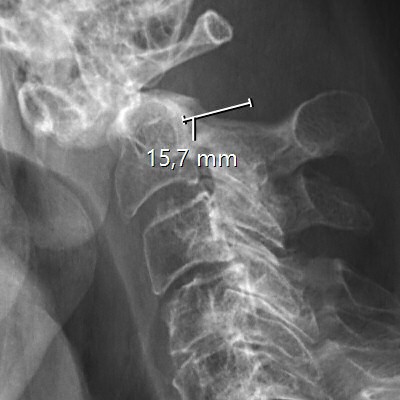

Provokationsröntgen som visar instabilitet vid densfraktur typ 2